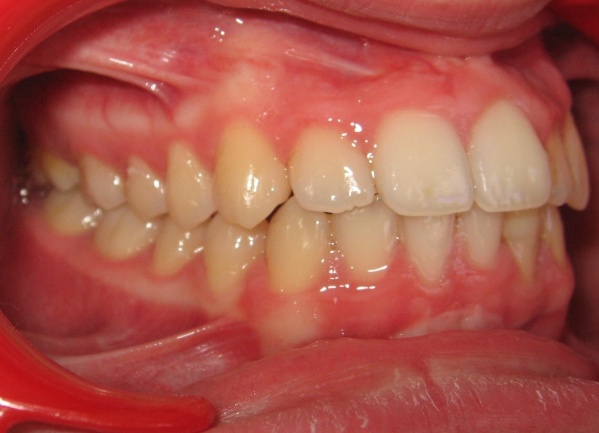

2 - Appareillage utilisé : expansion palatine et multiattaches

Cette étape montre l’utilisation d’un disjoncteur palatin pour élargir le maxillaire. Contrairement à la mandibule, le palais présente une suture médiane, véritable joint de croissance, que l’on peut activer chez l’enfant ou l’adolescent. En écartant progressivement les deux moitiés du maxillaire, on crée un gain d’espace réel, non dentaire. Cela permet de rétablir une largeur d’arcade suffisante, sans extraction, en amont de l’alignement multiattaches.